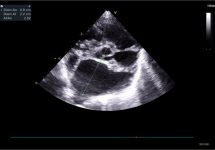

Pregunta 2

En un paciente con enfermedad valvular degenerativa mitral, en estadio C con diagnóstico previo de edema pulmonar, tras el tratamiento con furosemida, su perfil de flujo transmitral previo mostraba una pseudonormalización, con una velocidad pico E de 1,1 m/s. En la revisión, este es ahora su perfil de flujo transmitral. ¿Qué está pasando? ¿Qué más podemos hacer por el paciente?

Existe una progresión de la patología hacia una disfunción diastólica restrictiva, con un aumento de la velocidad pico E hasta 1,76 m/s, lo que indica que el paciente es refractario al tratamiento. Posiblemente continúe con frecuencias respiratorias elevadas. Habría que reevaluar si existe resistencia a los diuréticos y trabajar en reducir la poscarga (presión arterial). Además, según la edad del paciente, podría ser candidato a cirugía mitral edge-to-edge (si cumple criterios anatómicos y funcionales) y, en caso de no ser idóneo, podría considerarse la septostomía auricular.